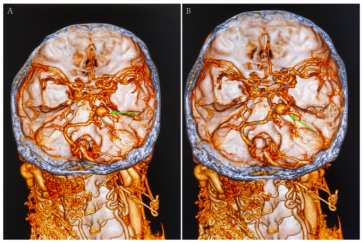

Revolutionizing Chronic Subdural Hematoma Care Through Advanced Diagnostics and Treatment

Chronic Subdural Hematoma: A Shifting Landscape in Neurosurgical Care The management of chronic subdural hematoma (CSDH) has been a topic of heated discussion in the healthcare community for many years. With an annual incidence that ranges from 1.7 to 20.6 per 100,000 people—and climbing due to an aging global population and increasing use of anticoagulant […] More